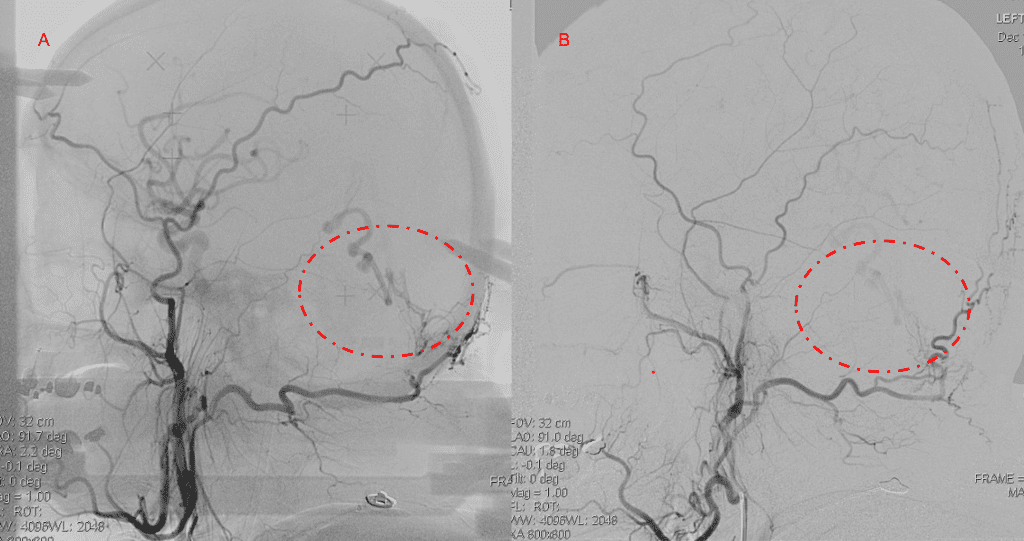

Figure 4. Left ECA AP and Lateral angiograms Pre (A and B) and Post NBCA embolization (C and D) Demonstrate near complete obliteration of Left Occipital Artery Fistulas.